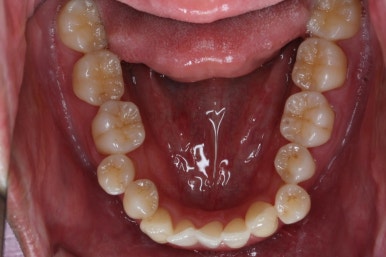

부산비수술교정 키다리아저씨치과에서 시행한 이번 치료의 결과입니다.

아랫니 갯수가 모자라고 중앙이 맞지 않았고 짝이 안맞는 상황이었으나 비교적 잘 마무리를 했어요.

거꾸로 물리는 상황이 개선되었기 때문에 앞니나 어금니의 교합은 이전과 비교할 수 없을만큼 좋아졌지요.

화살표는 사랑니인데요. 이 분의 경우 아래 앞니가 1개 없고, 1개를 추가로 뽑아서 윗니 대비 아랫니가 총 2개 모자란거죠.

운이 좋게도 이 분은 사랑니까지 잘 나와있던 상태라 내버려두기 아까워 함께 가지런하게 해주고 사용하실 수 있게 해드렸어요.